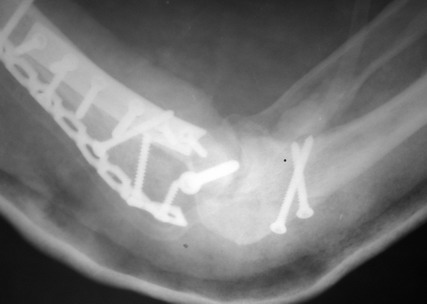

Примерный случай, только перелом был открытый, в задне-медиальной стороне рана около 2 см по характеру "изнутри кнаружи", неврологический статус со слабостью сгибания мизинца, также слабая абдукция и аддукция указательного пальца и сгибания в кисти.

Больному сделали обработку и наложили временный аппарат внешной фиксации плечо-предплечье.

На шестой день сделали открытую репозицию чрезлоктевым доступом двумя locking plate, локтевой нерв был ушибленным, после операции положительная динамика в Flexor Carpi Ulnaris. Фиксацию локтевого отростка произвели tension band technique с дополнительным шурупом.

Этапы операции на снимках....